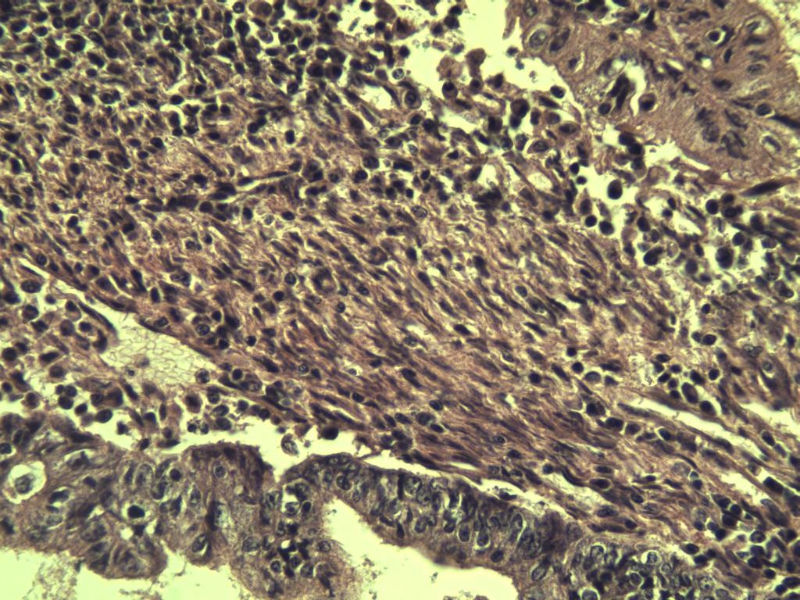

女,57岁,全切子宫一个,宫体体积 9 × 8 × 7 cm3,肌壁厚 2.5 cm,内膜菲薄,部分区域增厚达 0.4 cm(约3*2.5cm区域)。 请问各位老师  这个可以诊断子宫内膜癌了吧?      深肌层没有看到浸润。

患者因"发现下腹部包块1月多"入院  宫体体积 9 × 8 × 7 cm3,肌壁厚 2.5 cm,内膜菲薄,部分区域厚 0.4 cm(约3*2.5cm)。宫颈结构不清,长约 2.5 cm,表面欠光滑。临床诊断宫颈宫腔积液.

宫内膜样腺癌

筛状、迷路样结构

间质消失或者纤维性间质

子宫内膜样腺癌

高分化子宫内膜样癌。浸润浅肌层(深度<1/3肌层)。根据FIGO2009分期,子宫内膜癌局限于内膜层和<1/2肌层,都属于IA期。二者处理不再区别对待。